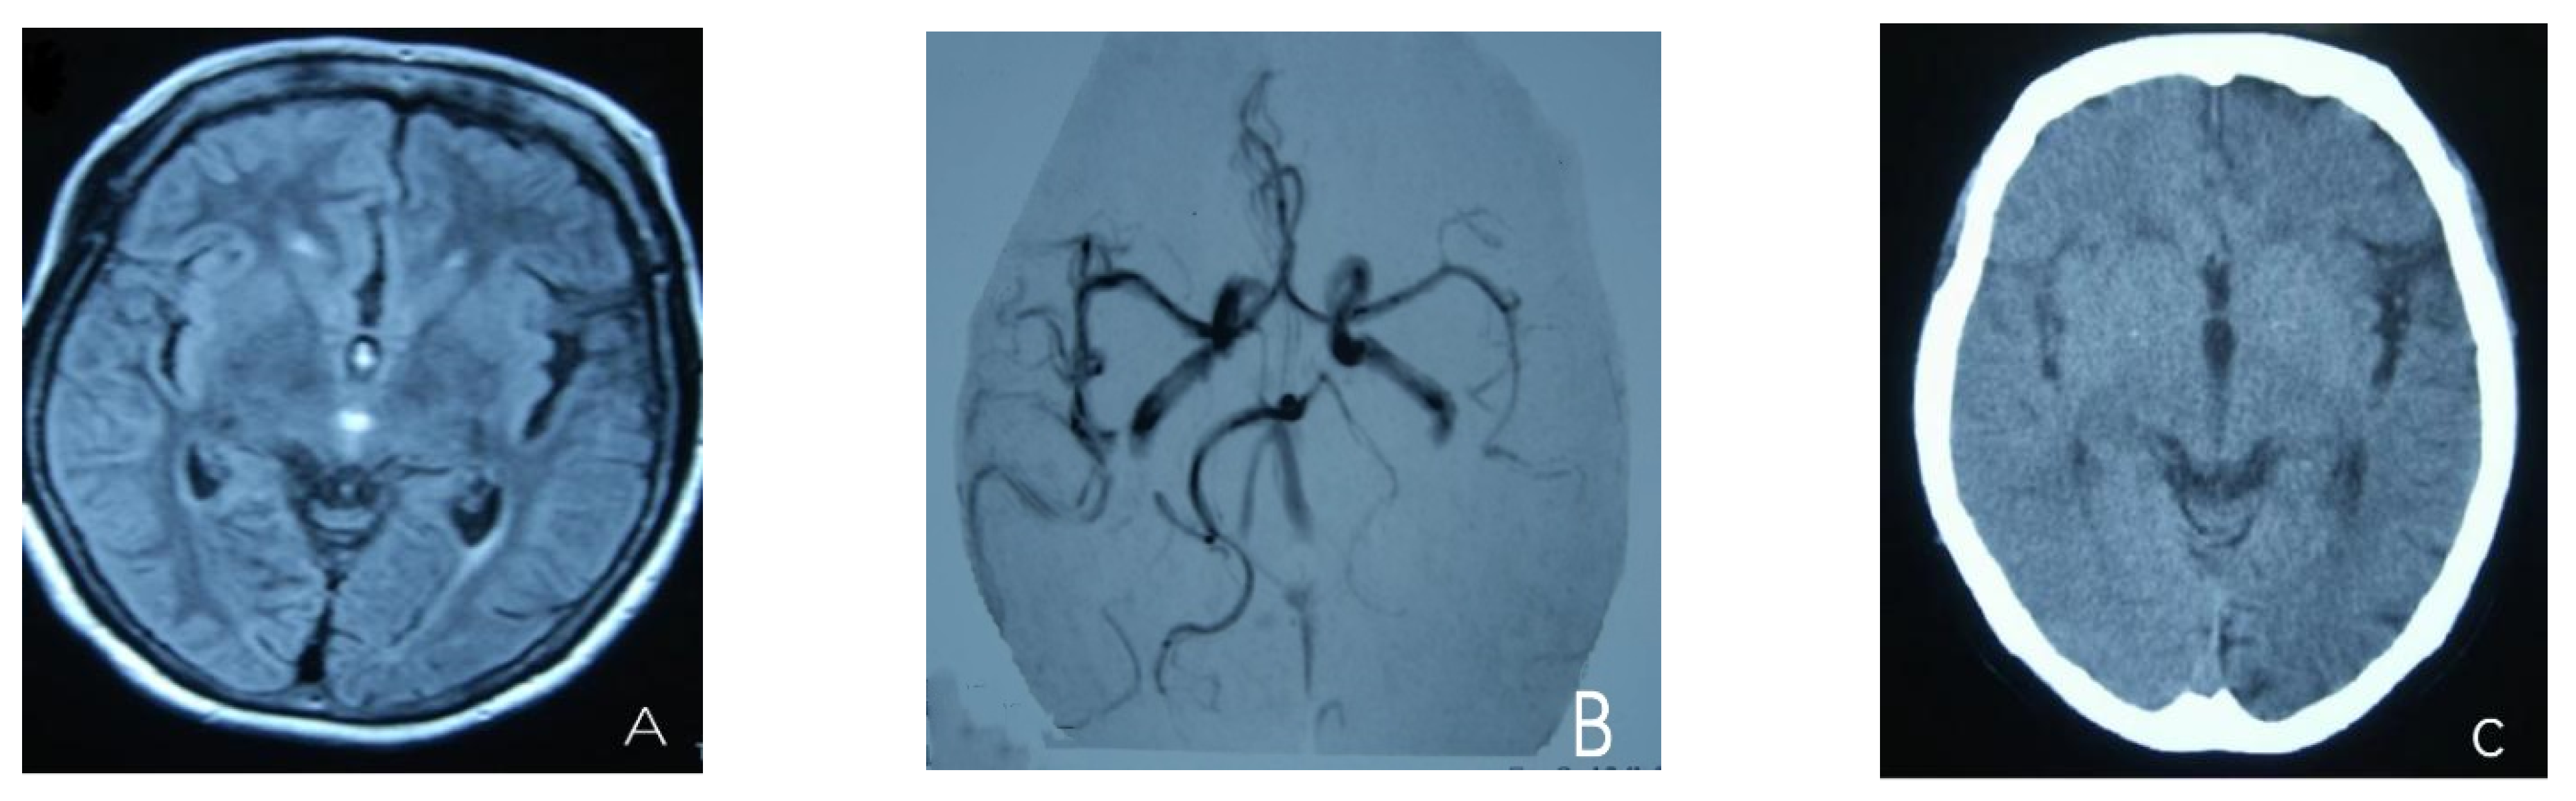

At the age of 51, she had a migraine attack with weakness in the left limb. The headache became increasingly serious, so she was admitted to a hospital six days after the attack. Upon admission, she had severe headaches and left limb weakness, and the neurological examination revealed left hemiparalysis with muscle strength at 3/5 by manual muscles testing (MMT). A brain MRI (magnetic resonance imaging) on day two of admission revealed cortical swelling in the right cerebral hemisphere (Figure 1A), and on the day three of admission, the magnetic resonance angiography (MRA) showed a slight decrease in the branches of the left middle cerebral artery (MCA). The main trunk of the left posterior cerebral artery (PCA) was slender contralateral, and its branches were significantly reduced contralaterally (Figure 1B). Symptoms persisted. On day five of admission, the patient had a focal epileptic seizure, which was followed by two more seizures. Subsequently, the patient’s left limb weakness gradually worsened, the neurologic examination revealed left hemiparalysis with muscle strength at 0/5 by MMT, and she gradually developed unconsciousness to light coma. Brain CT scans during coma revealed swelling of the right cerebral cortex (Figure 1C). Contrast-enhanced brain MRI showed swelling and diffuse enhancements in the cortex of the right cerebral hemisphere (Figure 1D). Perfusion-weighted imaging (PWI) showed right hemisphere hyperfusion (Figure 1E). Based on her medical history and presentation at admission, a lumbar puncture was performed, and the cerebrospinal fluid pressure (CSF) was 204 mm H2O. The biochemical and cytologic examination of the CSF revealed normal chloride, glucose and cell counts and classifications, in addition to normal protein levels. The CSF tested negative for bacteria, viruses, fungi and autoimmune encephalitis. Whole-exome sequencing showed a missense mutation (c.2473G > A, p.Glu825Lys) in exon 18 of ATP1A2. Based on a series of tests, the patient was diagnosed with FHM2 caused by a pathogenic ATP1A2 mutation. During hospitalization, we dehydrated the patient, gave the patient paracetamol for symptomatic treatment and an intramuscular injection of phenobarbital to control seizures. On the 15th day after admission, consciousness and hemiplegia improved, and the headache was relieved; the patient was discharged after 22 days. She was back to normal, and at later follow-up, the patient’s brain MRI (Figure 2A), contrast-enhanced brain MRI (Figure 2B), PWI (Figure 2C) and computed tomography angiography (CTA) all returned to normal (Figure 2D). The time course diagram of the disease in our patient is presented in Figure 3.

Figure 1.

(A) Cortical swelling in the right cerebral cortex (the 2nd day); (B) the MCA and PCA branches decreased (the 3rd day); (C) swelling of right cerebral cortex (the 7th day); (D) swelling and diffuse enhancement in the cortex of the right cerebral hemisphere; (E,F) right hemisphere hyperfusion.